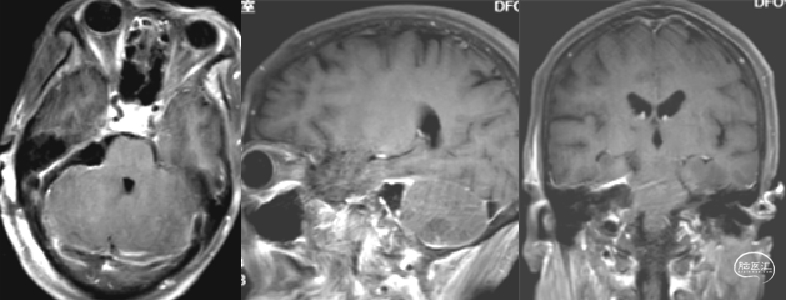

右侧桥小脑角区脑膜瘤切除术:

患者信息:患者女,69岁,因头部不适到医院就诊,在院做MRI检查,影像结果显示:右侧桥小脑角区可见一大小约30.1mm x 18.5mm x 24.9mm的不规则团块影,呈T1等/低信号T2等信号,T2FIair呈低/稍高信号,DWI呈等/稍高信号,轮廓较清晰,临近右侧小脑半球受压。

右侧桥小脑角区脑膜瘤切除术:

患者信息:患者女,69岁,因头部不适到医院就诊,在院做MRI检查,影像结果显示:右侧桥小脑角区可见一大小约30.1mm x 18.5mm x 24.9mm的不规则团块影,呈T1等/低信号T2等信号,T2FIair呈低/稍高信号,DWI呈等/稍高信号,轮廓较清晰,临近右侧小脑半球受压。